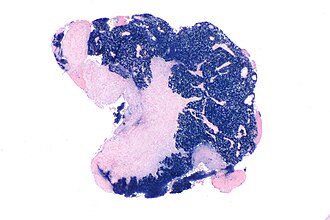

File:Nasopharyngeal carcinoma - EBER -- very low mag.jpg

Micrograph showing an EBER (Epstein-Barr virus (EBV)-encoded small RNAs) positive nasopharyngeal carcinoma. Epstein-Barr virus is a virus that causes cancer. (WC)